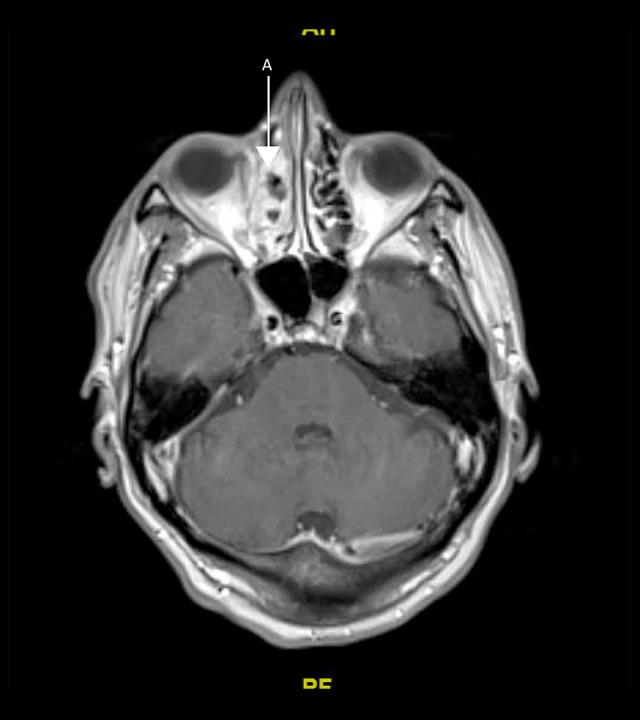

BACKGROUND We present a case of invasive sinusitis with rhinocerebral infection in a patient who had mild symptoms of COVID-19 infection and did not receive any immunosuppressive therapies. CASE REPORT A 49-year-old man with a history of uncontrolled diabetes presented to the hospital with multiple generalized tonic clonic seizures. He had recently been diagnosed with mild COVID-19 and was treated at home with supportive care only. He was found to have cerebritis in the right frontal lobe along with right fronto-ethmoid sinusitis. He underwent extensive testing with nasal endoscopy with gram stain and culture, cryptococcal studies, 1-3-Beta-D glucan, blood cultures, fungal CSF studies, Lyme disease, HIV, Fungitell assay, and galactomannan studies, which were all negative. He was started on i.v. antibacterial therapy with cefepime, vancomycin, and metronidazole along with amphotericin B. After 2 weeks, his repeat imaging revealed progression of cerebritis along with new early abscess. Given these findings, his antibiotics were changed to meropenem and the amphotericin B dose was increased. He was recommended debridement and sinus surgery but refused. During the course of treatment, he developed acute kidney injury and was switched to Posaconazole. Unfortunately, the patient decided to leave against medical advice 6 weeks into admission. He was advised to continue Posaconazole and levofloxacin but he could only afford levofloxacin. He was then recommended long-term levofloxacin. He has since recovered, with resolution of cerebritis noted in follow-up imaging 1 year later. CONCLUSIONS Our patient had mild COVID-19 infection and presented with secondary infective complications, which are usually associated with an immunocompromised state, despite receiving no immunosuppressives. It is imperative that all clinicians treating COVID-19 be watchful for fungal or bacterial co-infections in patients with active SARS-CoV-2 infection, even if the presenting symptoms are mild, particularly if other risk factors are present.

一名 49 岁男性,有未控制的糖尿病病史,因多发性全面强直阵挛发作到医院就诊。他最近被诊断为轻度 COVID-19,仅在家接受支持治疗。他被发现右额叶脑炎症伴有右额窦-筛窦炎。他接受了广泛的检查,包括鼻内镜革兰氏染色和培养、隐球菌研究、1-3-β-D 葡聚糖、血培养、真菌性 CSF 研究、莱姆病、HIV、Fungitell 检测和半乳甘露聚糖研究,结果均为阴性。他开始接受头孢吡肟、万古霉素和甲硝唑联合两性霉素 B 的静脉抗菌治疗。2 周后,他的重复影像学检查显示脑炎症进展,并出现新的早期脓肿。鉴于这些发现,他的抗生素改为美罗培南,并增加两性霉素 B 的剂量。他被建议行清创术和鼻窦手术,但被拒绝。在治疗过程中,他发生急性肾损伤,改为伏立康唑。不幸的是,患者在入院 6 周后决定出院。他被建议继续服用伏立康唑和左氧氟沙星,但他只能负担得起左氧氟沙星。然后建议他长期服用左氧氟沙星。1 年后的随访影像学检查显示脑炎症已消退,他已康复。